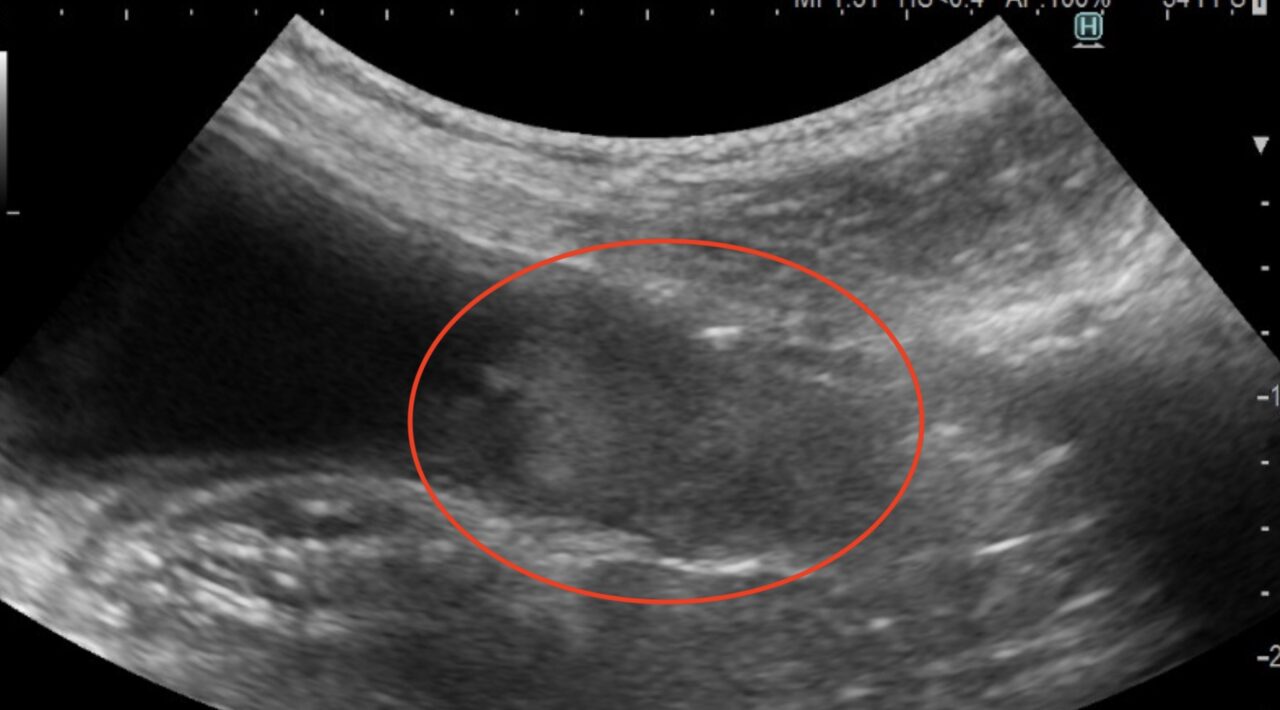

・超音波検査:がんの大きさや広がり、リンパ節転移の評価

膀胱の移行上皮癌の超音波画像(赤丸)